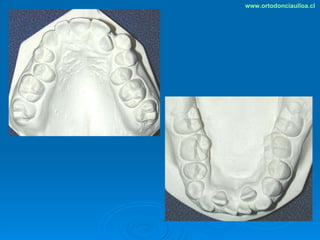

Este documento presenta dos casos clínicos de pacientes que recibieron tratamiento de ortodoncia. El primer caso fue de una paciente femenina de 14 años con apiñamiento dental y mordida cruzada que fue tratada mediante extracción de premolares y alineamiento dental. El segundo caso fue de un paciente masculino de 14 años con clase II esqueletal y desarmonía dentomaxilar que fue tratado con extracción de premolares y corrección de mordida. Ambos casos mostraron mejoría después de 3 años de tratamiento.